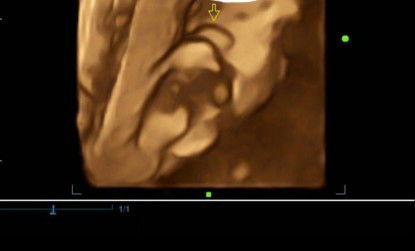

Baby gender

Hi mga mamshie. Tingin niyo po ano gender niya? Salamat sa sasagot.

Mukhang girl wala namn kasing itlog

girl?